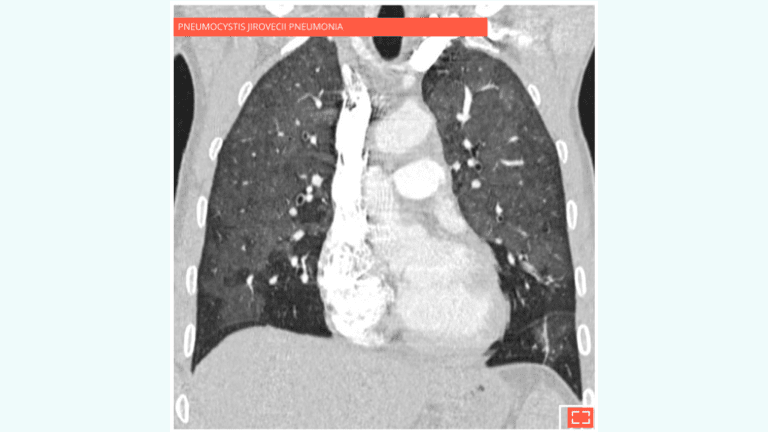

2. Diffuse ground-glass opacity

Diffuse ground-glass opacity of the lung sparing subpleural areas.